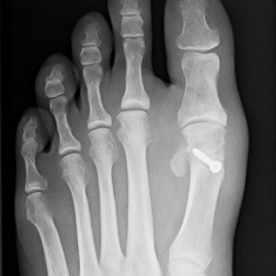

12) Hallux valgus

Häufigste und bedeutendste Zehendeformität mit seitlicher Abweichung der Großzehe im Grundgelenk. Es findet sich eine häufige Kombination mit einer Hammer- und Krallenzehe. Die konservative Therapie, meist im Frühstadium, umfasst die Druckentlastung des Großzehenballens, Barfußlaufen, ringförmige Schaumstoffpolster und Einlagenversorgung.

In fortgeschrittenen Fällen ist in der Regel eine operative Therapie mit Stellungskorrektur der Großzehe notwendig.